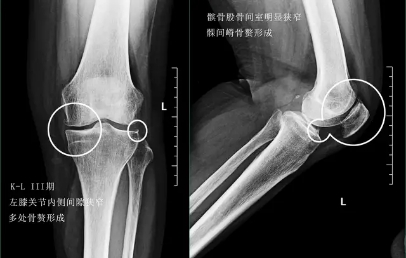

前面已经说到骨关节炎会导致骨赘的形成以及关节间隙的狭窄,所以我们依靠膝关节x片子来初步判断骨关节炎的病情,通常我们采用K_L分期判断病情。

三期患者:3期的患者不仅有了骨赘大量形成,而且关节间隙已经开始发生了明显的狭窄,患者的症状会越来越严重,很多会表现出来蹲起的疼痛,甚至有的患者不能长时间的行走,否则次日关节就会有明显的肿胀,有的患者在屈伸关节的过程当中会听到响声,类似于冬天我们用脚踩雪的那种响声。

此时我们只有通过进行关节置换手术的办法,才能帮助患者来解决痛苦。医生也知道很多患者不想做全膝关节置换术,所以说现在也研究出来单髁的置换手术,也算是一种保膝治疗。